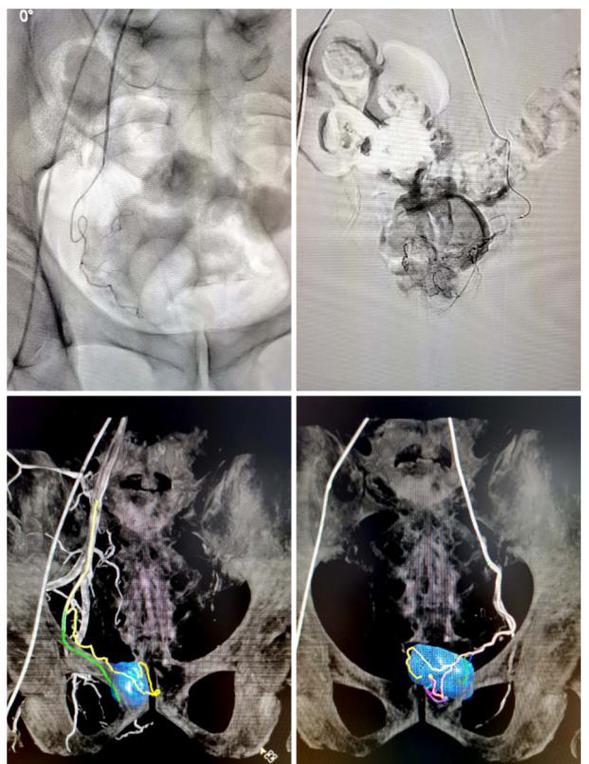

术中左侧前列腺动脉造影结果

术中右侧前列腺动脉造影结果